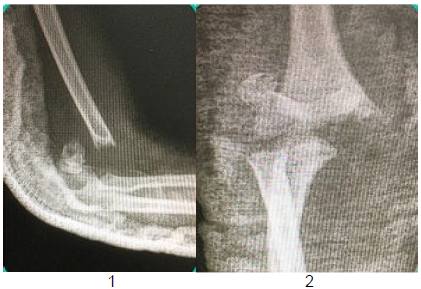

Paciente de 4 anos sofre queda do pula-pula e vem ao pronto-socorro com dor e deformidade do cotovelo direito. Faz as seguintes radiografias:

Fonte: COHEN, Moisés. Tratado de ortopedia. São Paulo: Editora Roca, 2007.

Qual é, respectivamente, a conduta e o nervo mais frequentemente lesado nesse tipo de fratura?